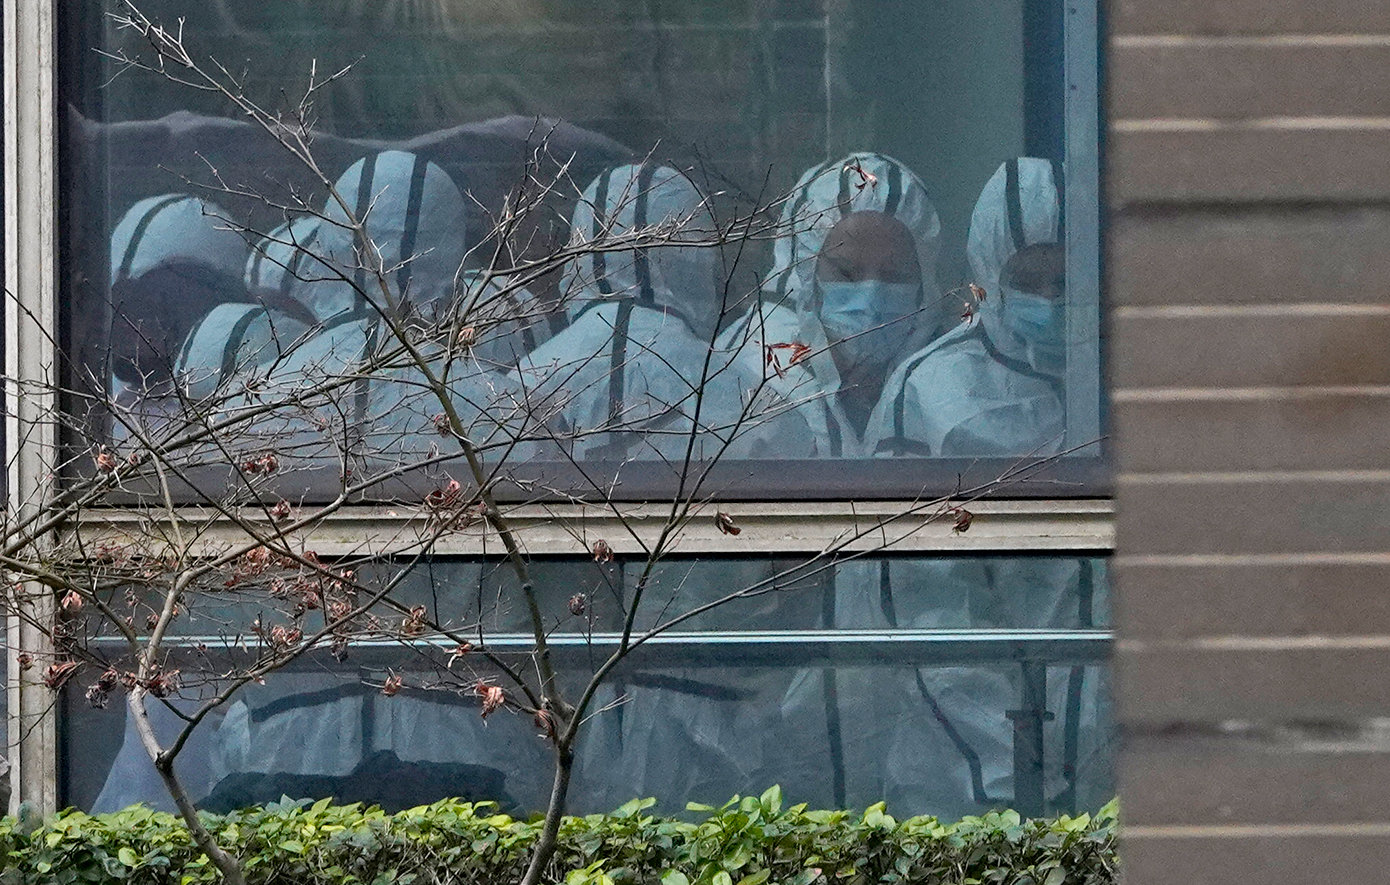

Ο κορονοϊός ανήκει στην κατηγορία των ιών RNA που χτυπούν θηλαστικά και πτηνά. Οι κορονοϊοί προκαλούν κυρίως αναπνευστικές λοιμώξεις οι οποίες μπορεί να είναι ήπιες αλλά μπορεί να αποδειχθούν και μοιραίες. Οι ήπιες ασθένειες στον άνθρωπο περιλαμβάνουν περιπτώσεις κοινού κρυολογήματος, ενώ οι θανατηφόρες περιπτώσεις προκαλούνται από τις λοιμώξεις σοβαρού οξέως αναπνευστικού συνδρόμου – ΣΟΑΣ (διεθνώς γνωστό ως SARS), η οποία άρχισε το 2002 στην Κίνα, το αναπνευστικό σύνδρομο της Μέσης Ανατολής το 2012 (MERS) και το σοβαρό οξύ αναπνευστικό σύνδρομο τύπου 2 - Covid-19, η οποία προκάλεσε την πανδημία κορονοϊού 2019–21. Για πρώτη φορά ο ΠΟΥ στις 14/01/2020 προειδοποίησε για το ενδεχόμενο εξάπλωσης του νέου κορονοϊού από την Κίνα και την πόλη της Γουχάν όπου και πρωτοεμφανίστηκε, εκτός συνόρων.

Ο νέος κορονοϊός SARS-CoV-2 και η πανδημία που προκάλεσε η ασθένεια Covid-19 έχει αποδειχθεί η πλέον θανατηφόρα για την ανθρωπότητα, μετά την ισπανική γρίπη, καθώς πλήττει επί 2 χρόνια σφοδρά όλη τη Γη κοστίζοντας τη ζωή σε πάνω από 5 εκατομμύρια ανθρώπους. Η πανδημία έχει πλήξει σφοδρά και την Ελλάδα η οποία έχει καταγράψει πάνω από 16.000 θανάτους ενώ κοντά στις 900.000 είναι τα καταγεγραμμένα κρούσματα.